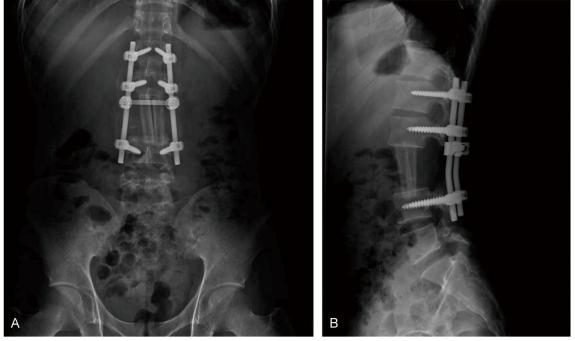

We report here on a case of a 23-year-old male who received en block spondylectomy for a vertebral Ewing's sarcoma at our hospital. Nine days after surgery, he presented with severe back pain and motor weakness of the lower extremities. Based on the physical examination and the computed tomography scan, he was diagnosed with acute cauda equina syndrome that was caused by compression from an epidural hematoma. His neurological functions recovered after emergency evacuation of the hematoma. This case showed that extensive surgery for a malignant vertebral tumor has a potential risk of delayed epidural hematoma and acute cauda equina syndrome and this should be treated with emergency evacuation.

我们在此报告一例23岁男性患者,其在我院因椎体尤文肉瘤接受了整块脊椎切除术。术后九天,他出现了严重的背痛和下肢运动无力。根据体格检查和计算机断层扫描,他被诊断为急性马尾综合征,由硬膜外血肿压迫所致。血肿紧急清除后,他的神经功能得以恢复。该病例表明,恶性椎体肿瘤的广泛手术有发生延迟性硬膜外血肿和急性马尾综合征的潜在风险,对此应进行紧急清除治疗。